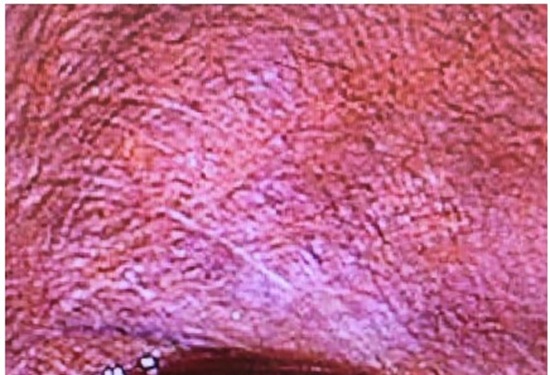

Patients (case 1, 2, 5, and 7) treated by LHIPEC alone were alive with WDPM (case 2, 5, and 7) from 11 to 77 months or without WDPM (Case 1) after 92 months (Table 2). PCI of case 1 at the 1st LHIPEC was 3, but it was 0 at the second laparoscopy, performed 6 months after the 1st LHIPEC. PCI of case 2 at the 1st LHIPEC was 30 (Figure 9), and WDPM was completely disappeared at the 2nd laparoscopy (Figure 10). However, PCI of case 7 was not changed at the 1st LHIPEC (PCI of 36) and 2nd LHIPEC (PCI of 36). PCIs of Case 3 and 4 at the 1st LHIPEC were 15, and 16, and those at the laparotomy became 3 and 13. Accordingly, complete resection could be done in the two cases, and they are alive without recurrence. In contrast, PCIs of case 8 and 9 at the laparotomy were 26 and 23, and those could not be reduced by LHIPEC and IP chemotherapy to the levels to perform complete resection. Additionally, small bowel mesentery in these 2 cases was diffusely involved, Case 8 died of mesothelioma recurrence in pleural cavity and abdominal wall, and the histology showed MPM (Figure 11). Case 9 is alive with mesothelioma recurrence in peritoneal cavity and the pathologic diagnosis was biphasic type of DMPM. Case 5 committed suicide.

Figure 10: Laproscopic finding of pelvic peritonealsurface six month after laparoscopic HIPEC and IP chemotherapy.